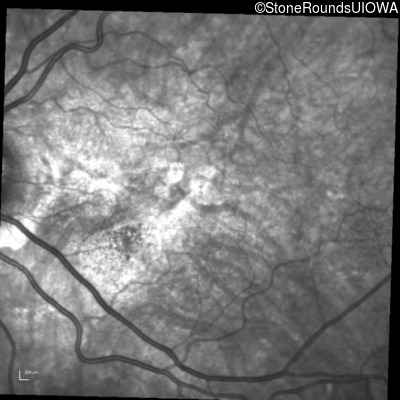

Infrared Fundus Photograph - Right - 20/20 -3 sc

Exemplar